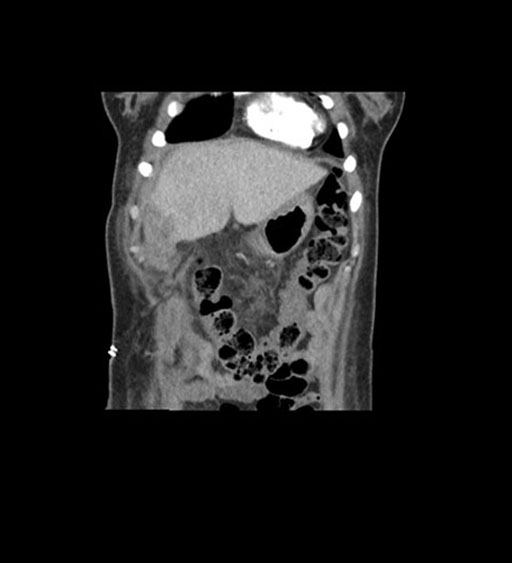

Axial Venous

Coronal Venous